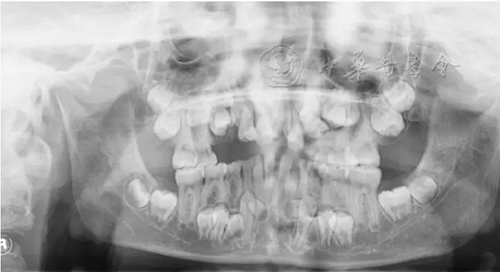

(1)疾病定義及口腔表現(xiàn):LCH是一組原因不明、以朗格漢斯細胞及其前體細胞克隆性增生為特點的疾病,又稱組織細胞增生癥X(histiocytosis X)。多見于20歲以下青少年。根據(jù)患者的發(fā)病年齡和臨床特點將其分為3型:嗜酸性肉芽腫、漢-許-克病和勒-雪病??谇活M面部常見的為骨嗜酸細胞肉芽腫,好發(fā)于下頜磨牙區(qū)與下頜角部位,病變主要為溶骨性破壞。早期表現(xiàn)為慢性炎癥和局部無痛性膨隆,病變區(qū)牙槽黏膜糜爛、潰瘍;牙齦充血,形成深牙周袋。隨著病變進展,出現(xiàn)牙齒松動加重,病變區(qū)鈍痛,進食時加劇,口臭明顯。拔除松動牙后拔牙創(chuàng)經(jīng)久不愈,觸碰牙槽窩時疼痛劇烈。影像學檢查可見骨內(nèi)圓形或橢圓形低密度影(圖2),直徑數(shù)毫米至數(shù)厘米不等,邊緣較囊腫模糊。頜骨內(nèi)病損常延伸至牙槽嵴,形成牙齒懸浮的特征性影像。牙槽骨包括牙槽中隔呈水平或垂直向吸收,牙根吸收。

圖2 4歲朗格漢斯細胞組織細胞增生癥患兒的曲面體層X線片,可見右側下頜骨大面積橢圓形低密度影